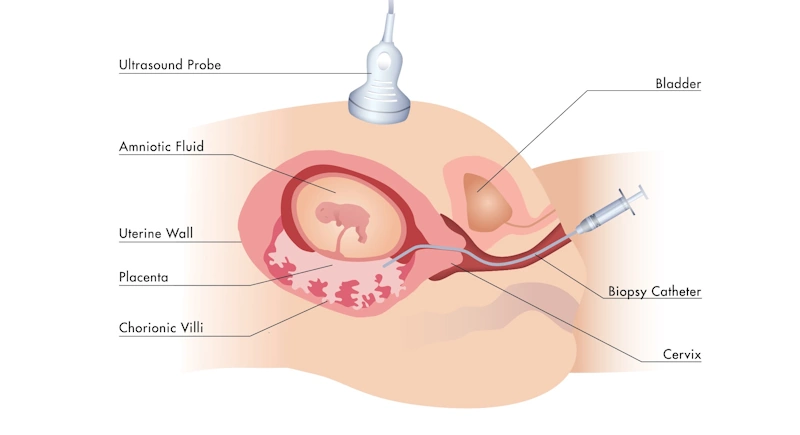

🧫 آزمایشهای تشخیصی تکمیلی

اگر نتیجهی غربالگری اولیه مشکوک یا مثبت باشد، ممکن است پزشک آزمایش CVS (نمونهبرداری از پرزهای جفتی) یا آمنیوسنتز را برای تشخیص دقیقتر توصیه کند.

این روشها معمولاً در مراکز تخصصی و تحت نظر پزشک مجرب انجام میشوند.

حتی اگر نتیجه غربالگری احتمال خطر را نشان دهد، نتیجه قطعی فقط از طریق آزمایشهای تشخیصی مشخص میشود.